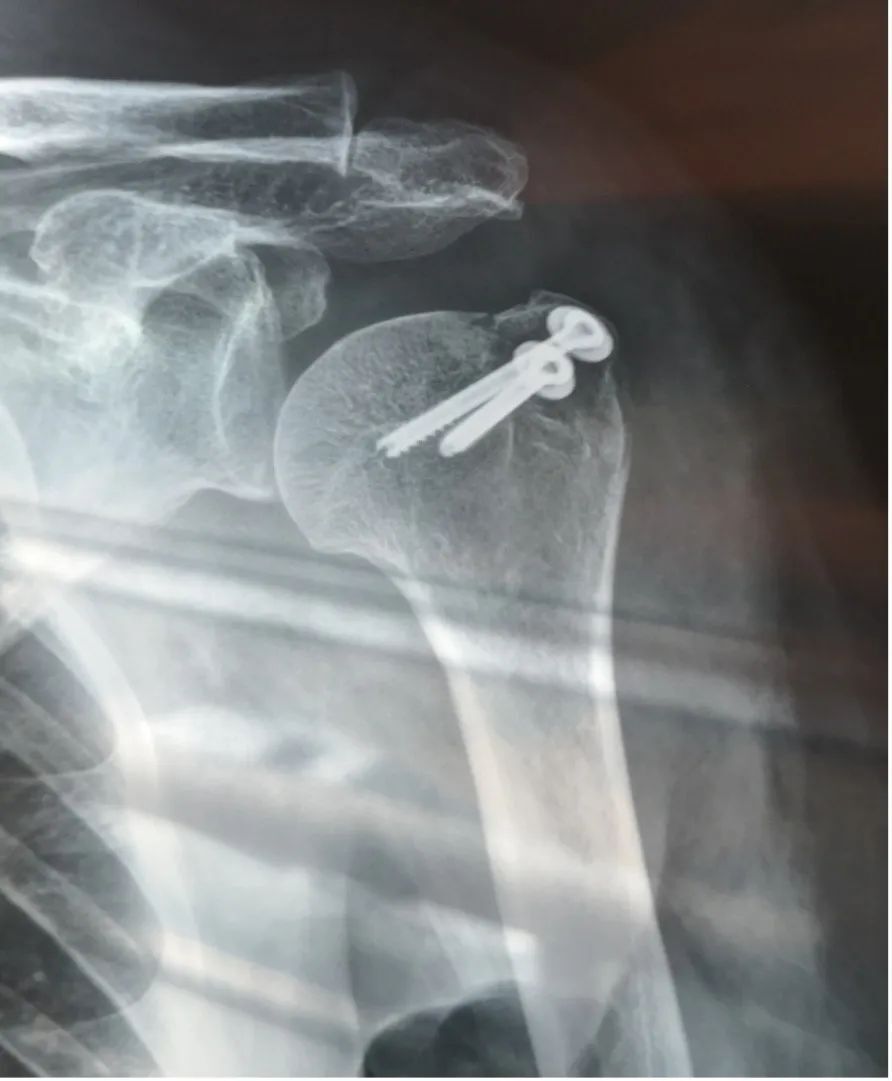

来到急诊科,首先是拍片,等了30分钟拿到结果,是脱位加骨折

左肱骨大结节骨折,左肩关节脱位丨作者供图

再次拍片:左肱骨大结节骨折,左肩关节半脱位。医生解释说,我左肩肌腱有撕裂,而且肱骨掉下来了一块,所以复位不完全,必须住院手术。

入院后第二天经磁共振进一步检查:左肱骨大结节骨折伴骨髓水肿、左肩关节前下盂唇损伤、肩胛骨骨髓水肿、左肩肩胛下肌腱和冈上肌腱损伤、左肩周肌群及皮下软组织广泛水肿、左肩腋囊水肿、左肩肱二头肌长头肌腱腱鞘滑膜炎……看来问题还真不少。